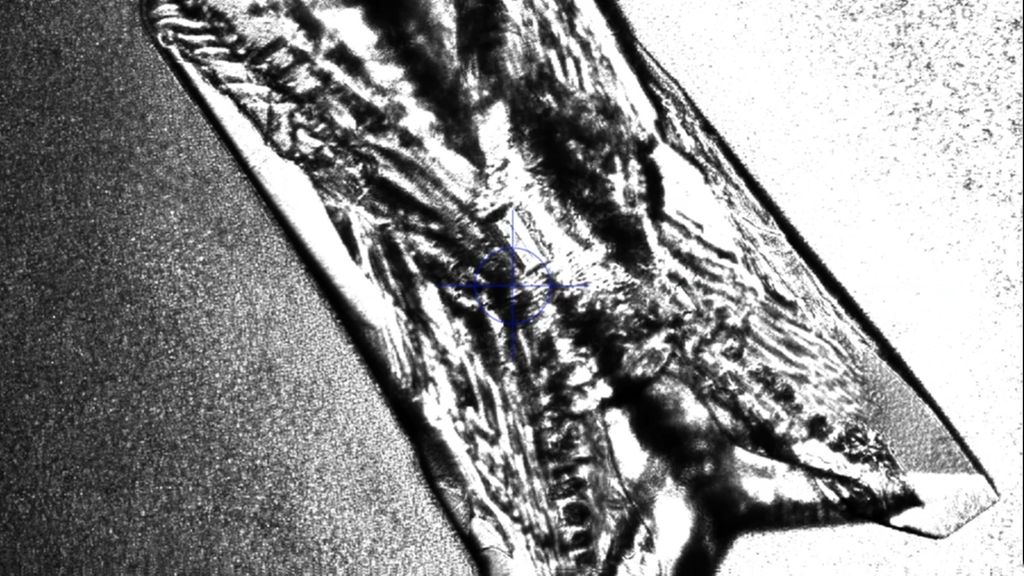

In Gegenwart von Urease produzierenden Bakterien wird Harnstoff im Urin zu Ammoniak und Kohlendioxid gespalten. Durch die Ammoniak- und CO2-Produktion und die darauffolgende Reaktion von CO2 mit H2O, die zu hohen Bicarbonatwerten führt, steigt der Urin-pH-Wert stetig an und pendelt sich schließlich bei 7,2–8,0 ein. Ammoniak wird dabei weiter hydrolysiert und bildet Ammoniumionen. Die basische Übersättigung des Urins führt bereits ab Urin-pH-Werten von 6,8 zu einer erhöhten Kristallisationsneigung von Kalziumphosphat zu Carbonatapatit. Zusätzlich kristallisiert im basisch übersättigten Urin ab einem Urin-pH-Wert >7,2 das basisch nur schwer lösliche Magnesium mit den Ammoniumionen zu Magnesiumammoniumphosphat (Struvit). Es bildet sich „Struvit-Apatit-Staub“ um die Urease produzierenden Bakterien. Sowohl in diesen Bakterien als auch in ihrer Umgebung kann es zur Kristallisation kommen. Die in den Bakterien gebildeten Mikrolithen können nach der Bakteriolyse den Grundstein für die Bildung von neuen Infektsteinen legen (Abb. 1 und 2).2,5

Abb. 1: Mikroskopische Darstellung eines Struvitkristalles durch Anzüchtung von Proteus mirabilis in artifiziellem Urin. Quelle: eigene Forschungsarbeit